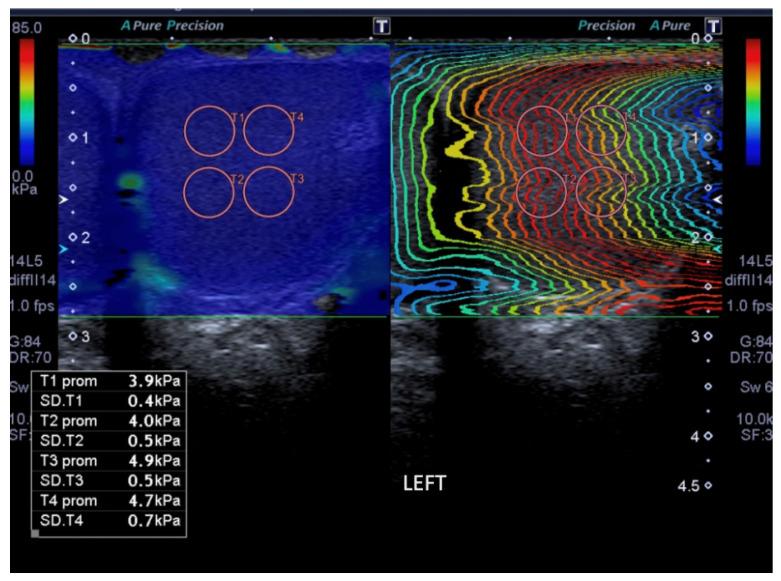

Ultrasound with shear wave elastography (SWE) was performed on 48 consecutive patients (96 testicles) referred following urology consultation for different reasons. A total of 94 testes were studied and distributed in three groups: testes with varicocele (group A, n = 19), contralateral normal testes (group B; n = 13) and control group (group C, n = 62). Age, testicular volume and testicular parenchymal tissue stiffness values of the three groups were compared using the Kruskal-Wallis test.

The mean age of the patients was 42.1 ± 11.1 years. The main reason for consultation was infertility (64.6%). The mean SWE value was 4 ± 0.4 kPa (kilopascal) in group A, 4 ± 0.5 kPa in group B and 4.2 ± 0.7 kPa in group C or control. The testicular volume was 15.8 ± 3.8 mL in group A, 16 ± 4.3 mL in group B and 16.4 ± 5.9 mL in group C. No statistically significant differences were found between the three groups in terms of age, testicular volume and tissue stiffness values.

Tissue stiffness values were higher in our control group (healthy testicles) than in patients with varicocele.